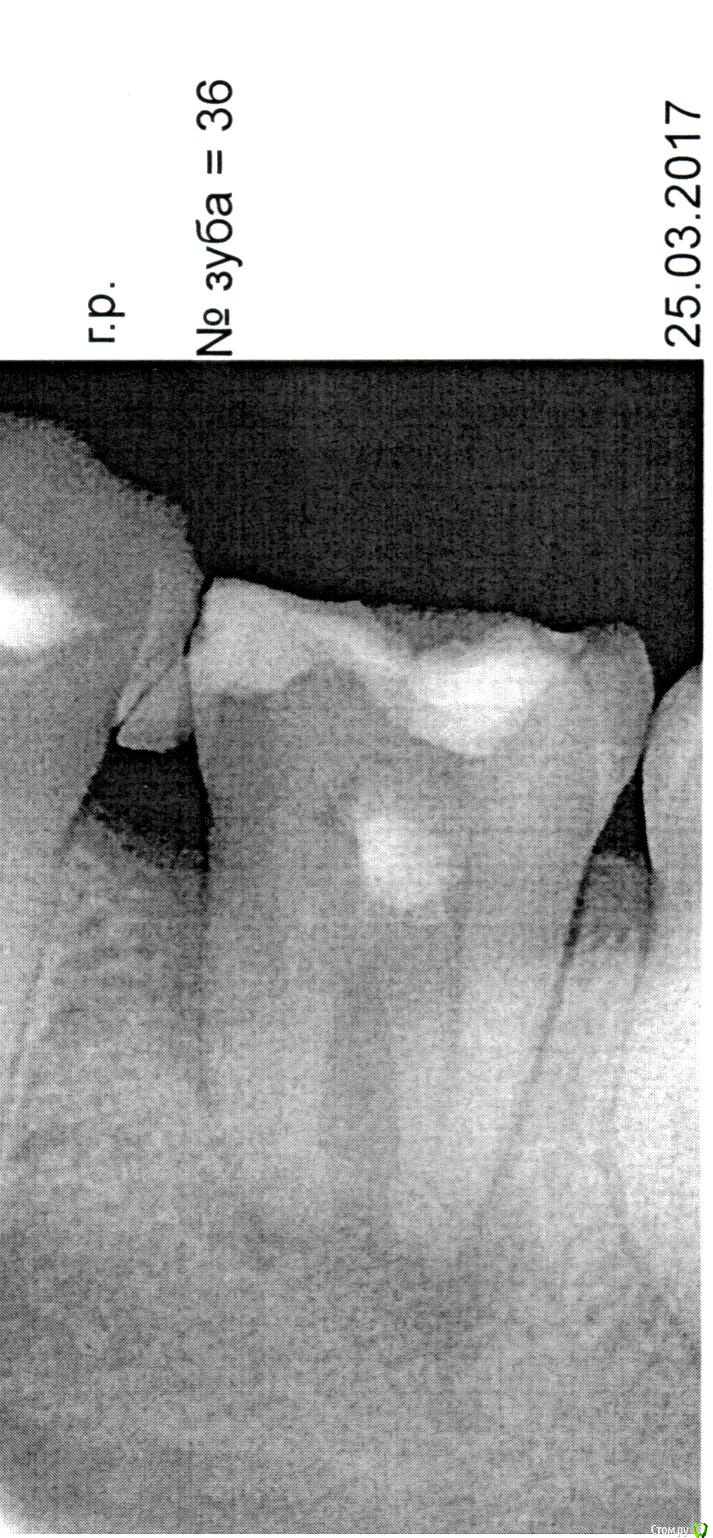

Андрей54 Опубликовано 27 марта, 2017 Поделиться Опубликовано 27 марта, 2017 (изменено) Добрый день!Подскажите, пожалуйста, обязательно нужно удалять зуб или его можно как-то вылечить?Снимок прилагаю. Изменено 27 марта, 2017 пользователем Андрей54 Ссылка на комментарий

Андрей54 Опубликовано 27 марта, 2017 Автор Поделиться Опубликовано 27 марта, 2017 В этом и вопрос, возможно ли его вылечить?Врач на приеме сказал, что зуб раскололся и лечению не подлежит, его только 100% удалять. Ссылка на комментарий

red_butler Опубликовано 27 марта, 2017 Поделиться Опубликовано 27 марта, 2017 В этом и вопрос, возможно ли его вылечить?Врач на приеме сказал, что зуб раскололся и лечению не подлежит, его только 100% удалять.Мы видим только снимок, причем плохого качества. Для окончательного ответа нужен очный осмотр. Ссылка на комментарий